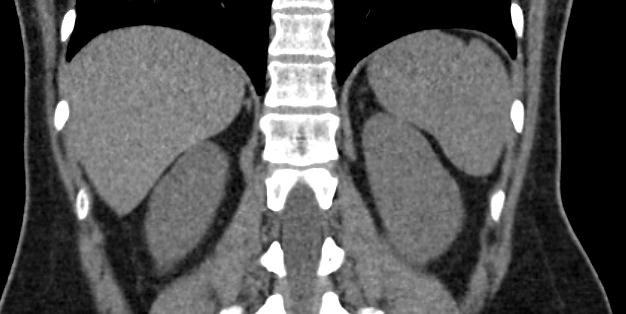

Мультиспиральная компьютерная томография селезенки – высокоинформативный инструментальный метод исследования, основанный на использовании рентгеновского излучения и позволяющий детально визуализировать паренхиму селезенки, состояние близлежащих органов и тканей, питающих ее кровеносных сосудов и лимфоузлов.

МСКТ селезенки проводится как с использованием контраста, так и без него. Контрастирование применяется для выявления патологических очагов, которые могут быть не видны при нативном исследовании. Для этого внутривенно вводится контрастный препарат, содержащий йод и накапливающийся в патологических очагах опухолевой и воспалительной природы.

Нативная КТ (бесконтрастное исследование селезенки) показывает структуру органа достаточно однородно, без выявления незначительных изменений. Для большей информативности делают КТ селезенки с применением контрастных веществ.

На томограмме можно увидеть:

- нарушение целостности селезенки;

- кисты и крупные опухоли;

- кальцинаты;

- травматические и посттравматические изменения селезенки

- кровоизлияния внутрь брюшной полости

- отклонения от нормальных размеров.

- дополнительные дольки селезенки.